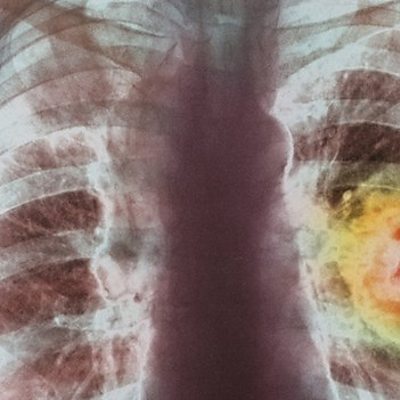

Lung cancer is the most common form of cancer in the world and the outlook has not improved much over time. Only 10% of patients live for another five years after a diagnosis, mainly due to it being spotted at a late stage. Tobacco causes 70% of lung cancer deaths, but you can get lung cancer without ever having smoked a single cigarette. Usually it is diagnosed by having an x-ray followed by a CT scan, but doctors at University College Hospital in London had the idea of trying to diagnose it by shining pure light on cells scraped from the inside of the cheek of people with lung cancer. Professor Samuel Janes recently presented the research at the meeting of the British Thoracic Society Winter meeting in London. Perinatal OCD Perinatal Obsessive Compulsive Disorder is a very distressing condition which often remains hidden and can have serious consequences for new mothers and their families. It is where pregnant women or new mothers fear contaminating their babies or find themselves plagued with thoughts that they might harm them, even though they will not ever do that. Clinical psychologist Fiona Challacombe, from the Institute of Psychiatry in London, tells Health Check more about the condition, along with Diana Wilson who experienced perinatal OCD with all four of her children. Epilepsy in Film The neurological disorder Epilepsy, is as old as the human brain. And yet it is still met with fear and ignorance. There are numerous kinds of epilepsy. The most widely known is the grandmal that involves a person falling to the ground and having a seizure. Many people will never have witnessed a person with epilepsy having a seizure and are likely only to have seen epilepsy depicted in film. But films showing seizures have tended to mirror the prejudices of society. A new film, Electricity, starring the former super model Agyness Deyn has been praised for its sensitive portrayal. The BBC’s Colin Grant reports on the new film and asks whether it will change audiences’ perception of epilepsy. (Photo: X-ray detecting lung cancer: Credit: Science Photo Library)